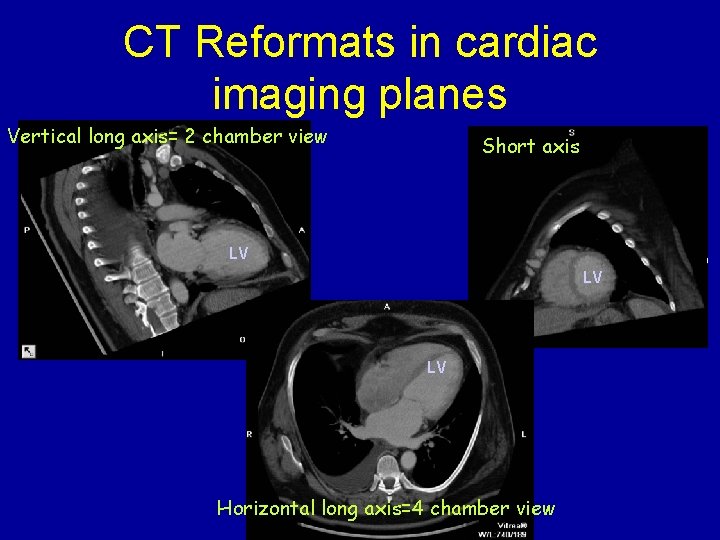

CT Reformats in cardiac imaging planes Vertical long axis= 2 chamber view Short axis LV LV LV Horizontal long axis=4 chamber view